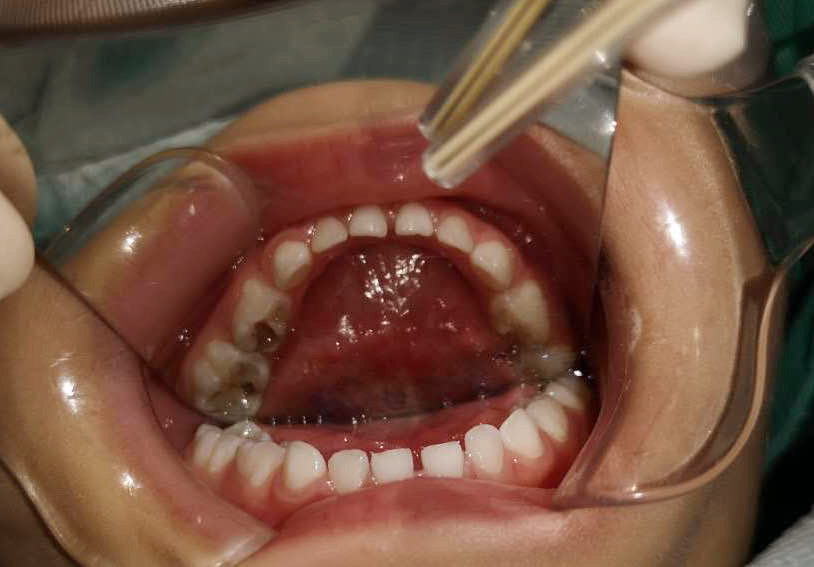

調(diào)節(jié)前